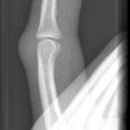

Bennett Fraktur

Bennett Fraktur mit geringer Dislokation